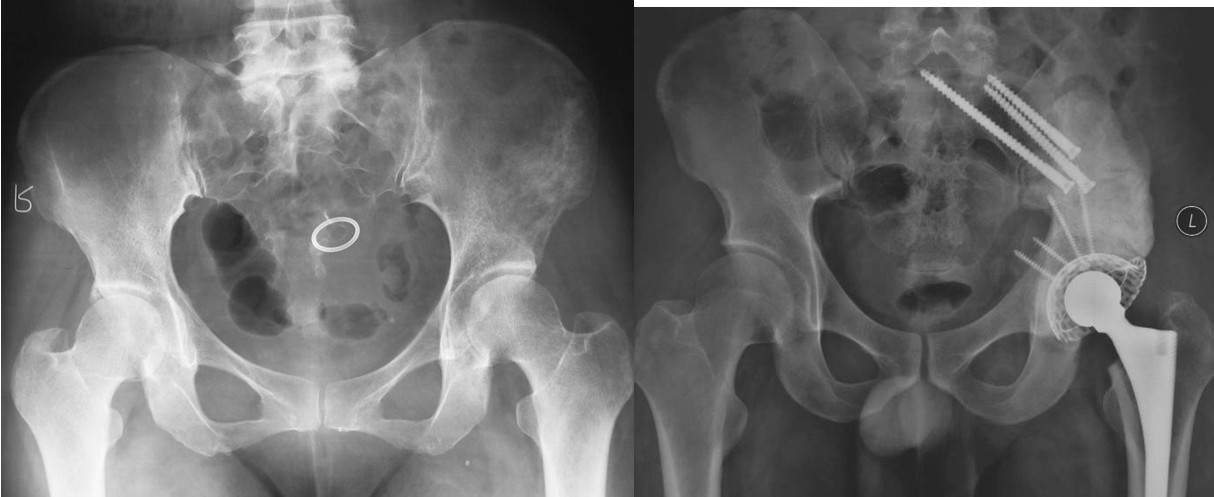

本组病例中不同部位髋臼转移癌的手术方式(图1):I型:髋臼下壁骨破坏、上壁及内、外侧壁完整, 采用肿瘤刮除、普通水泥型全髋置换术。II型:髋臼内、外侧壁破坏,上壁骨质完整, 采用带翼网杯+水泥型全髋置换术。 III型:髋臼上壁及内、外侧壁均破坏,采用肿瘤刮除后、骨水泥填充髋臼上壁骨缺损,带翼网杯+水泥型全髋或组合式人工半骨盆。IV型:孤立性骨盆转移, 以治愈为目的, 采用肿瘤整块切除,组合式人工半盆置换术。

Ⅳ型:为了达到治愈而需要进行整块的髋臼切除。对于部分单一髋臼转移的病例,以及髋臼周围骨质破坏范围较大的病变,在广泛切除肿瘤后,重建髋关节(内半盆切除)有时较为困难。在这些病例,可以选择马鞍式假体。这种方法最开始用于全髋关节置换术后的骨缺损,后来也用于原发或转移性髋臼肿瘤的治疗。也可以选用带有固定翼,能固定于残存髂骨和耻骨支的定制型髋臼假体(7-9)。这种假体制作前通常需要进行CT模拟重建设计。固定方式常用螺丝钉和骨水泥。有时想要应用定制型假体达到理想的固定位置较为困难。对于骨盆环的完整性重建,纵向稳定是极其重要的,同时要考虑人工假体在术中的可操作性。定制型骨盆假体为非组配式,其髂骨固定螺钉是单轴向的,不能根据术中截骨情况调整假体,固定也不够牢固。 我们设计使用的可调式半骨盆假体,其髂骨固定钉改为双轴向或多轴向固定,假体与骨之间的界面为垂直压力、而非剪力,增加了稳定性,同时可以根据髂骨截骨的高度选择颈长的臼杯,利于安装和保持骨盆平衡(10)。组配式骨盆假体还考虑到骨盆纵向和侧方的稳定因素, 尽量达到恢复骨盆环连续性和稳定性的目的。对于髂骨区和髋臼上缘的骨缺损重建,钉棒系统简单,易于操作,但固定钉在骨内的应力较大,容易在负重的情况下对骨质产生切割,尤其骨质疏松的病人固定更加不稳,因此需用骨水泥加强。由于组配式人工骨盆是一个组合装置,因而体积较小,便于软组织覆盖,伤口感染率大大下降。

图5,男,69岁,肾癌髋臼转移, Harrington IV型